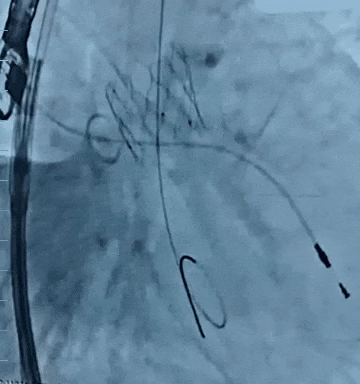

黄兵教授:反流新“瓣”法——自膨短瓣在单纯反流中的临床实践经验分享

武汉大学人民医院黄兵教授结合病例分享了ScienCrown自膨短瓣在单纯主动脉瓣反流(PAR)中的应用价值。CASE 1为主动脉瓣退行性变并重度PAR,术前CT示瓣环直径23.7mm,敞口流出道,无多平面锚定,STJ及升主可见明显扩张,属于TYPE 4型反流患者(指LVOT、瓣环和升主动脉均不能锚定的患者)。术中应用该款自膨短瓣出色完成窦部增宽单一瓣环平面锚定,锚定平面稳定,且区别于传统自膨瓣应用于PAR的“大oversize理论”,术中小oversize选择TAVTF 27mm瓣膜,进一步减少反流患者传导阻滞风险。最终造影示瓣膜位置与形态良好,无瓣周漏。

CASE 1:脱钩后造影